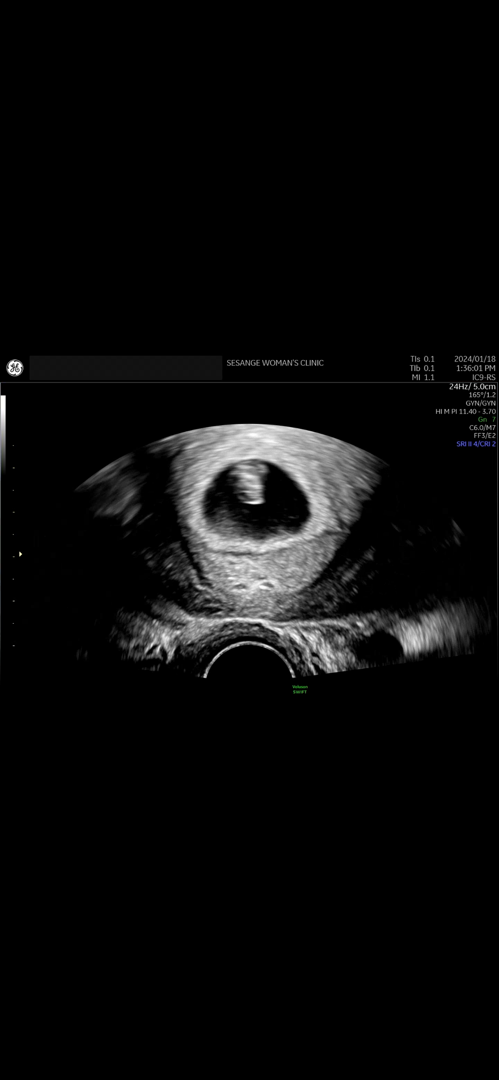

초음파 사진

이거 애기 옆모습인가여 ...?

흠 옆모습인지는 잘 모르겠는데 의사쌤은 별말 없으셨나요?!

네! 주수에 맞게 잘 크고있고 심장 소리도 규칙적이라고 하긴 하셨어요 .. 자궁도 건강하다고 하시긴 했는데 ㅠ